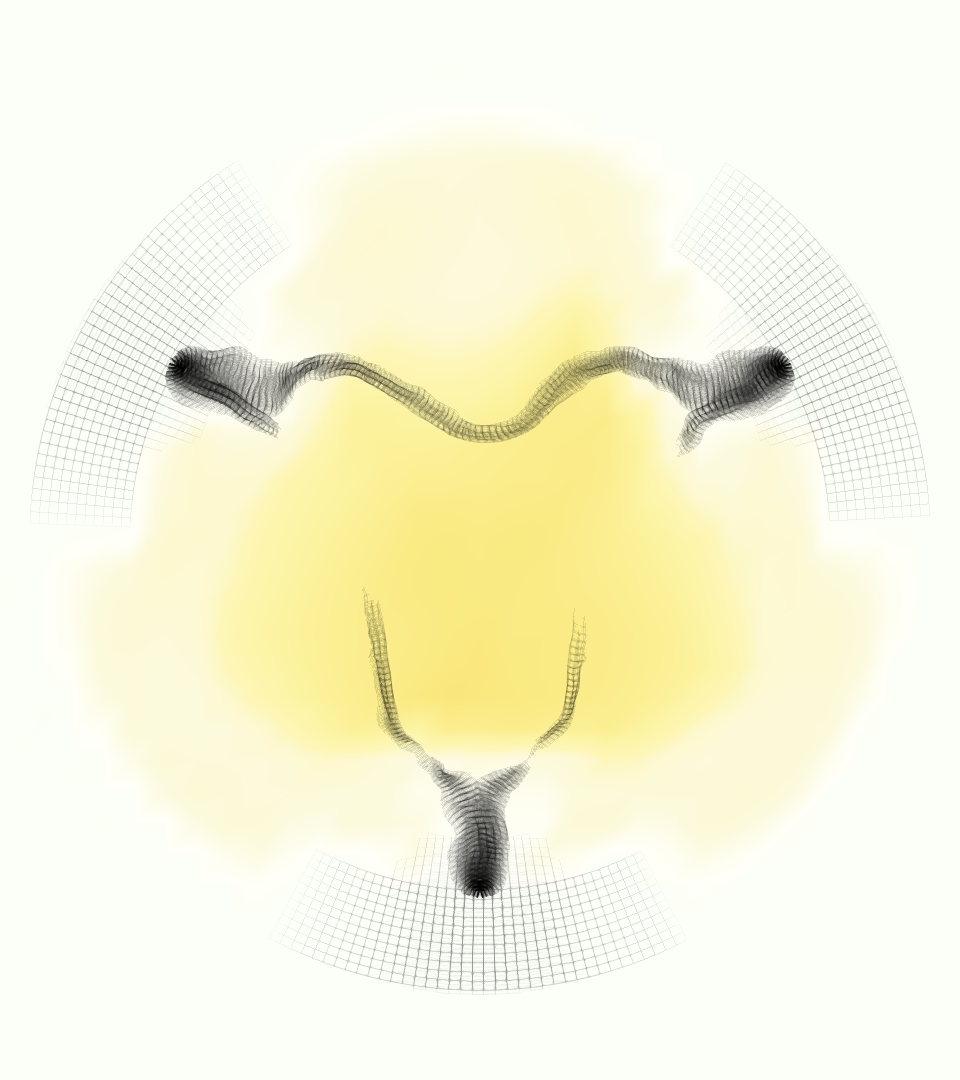

The gross morphology of the model valve that emerged from this process is shown in Figure 4. The free edge was 2.87 cm, corresponding to 3.3 cm in the predicted loaded configuration. After the pinching the leaflets together at the commissures, this left approximately 2.1 cm of free edge rest length per leaflet free to move independently of the other leaflets, within measurement error of ±0.1 cm from the free edge length of 2.2 cm measured on the prostheses. The leaflet rest height was 0.94 cm corresponding to a predicted loaded height of 1.44 cm. The measured leaflet height of 1.3 cm is nearly the predicted loaded height of 1.44 cm, which may be because the leaflets are so compliant in the radial direction, that pulling them flat to measure them achieved substantial stretches. The fiber orientation of the model runs from commissure to commissure and qualitatively matches experimental observations [38], though direct quantitative comparison is beyond the scope of this work. One minor limitation is that we do not add bending rigidity to the leaflets, beyond what emerges from the thickening process described above, and thus may not accurately capture leaflet flutter or other similar behaviors. Based on the thickness of mm, we estimated the mean tangent modulus at the predicted loaded stretches as dynes/cm2 circumferentially and dynes/cm2 radially. The prosthetic valve tissue is fixed in glutaraldehyde, and literature values for the fully-recruited circumferential tangent modulus of fixed porcine aortic valve tissue vary widely. Based on the experimental measurements of Billiar and Sacks and their constitutive law for valves fixed under 4 mmHg of pressure, we evaluated their constitutive law at the relevant stretches and and estimated the circumferential tangent modulus to be dynes/cm2 [6]. Rousseau et al. reported moduli ranging from to dynes/cm2, depending on the applied preload during fixation [36]. Sung et al. reported moduli ranging from to dynes/cm2, depending on fixation pressure [43]. Thus our estimated tangent modulus falls within the range of existing studies, so we considered our resultant modulus in good agreement given the complexity of the steps involved, phenomenological nature of the constitutive law and uncertainties in experiments. We do not have access to the precise material properties of the prosthetic valve, and further, the only literature we could find on the material properties of a similar prostheses reported the tangent modulus at one particular loading, which did not appear to be at a relevant stretch for comparisons with our model [19]. Thus, our model has material properties in a reasonable range for a fixed aortic valve prostheses (placed in the pulmonary position in our simulations), but it does not directly model the material properties of the prostheses.

We constructed the model vessel for FSI simulations from data from the MRI scans (Figure 4). The signal magnitude of 3D printed model material is distinct from the signal of the fluid in the scans, and we applied a thresholding operation to generate a three-dimensional model of the printed vessel surface. Using the MRI data ensured that the MRI and simulation coordinates were consistent in space and there were no alignment or registration errors. While using the files that generated the 3D printed model would have offered more spatial fidelity, the potential error in flow fields due to any mis-registration would have likely been much more substantial. Using Meshmixer (San Rafael, CA), we smoothed the mesh to remove stair-step effects and removed artifacts from the valve scaffold. We then remeshed to the desired edge length of 0.25 mm and extruded the model 0.25 mm and 0.5 mm to create a three-layer structure. As in the valve, this serves to eliminate the “grid aligned artifact” that can occur with pressure differences across thin membranes in the IB method [16]. Flow extenders of length 1 cm were added to the vessel at the inlet and both outlets to ensure that the normal to the vessel was aligned with the normal of the fluid box at the inlets and outlets. In FSI simulations, the vessel was held in place using target points, stiff springs of zero rest length that connect the current position of each model node to its desired position (Section 3.3). Additional linear springs are placed on each edge in the triangulated model. These springs are not meant to model a particular material and only serve to keep the vessel rigid and stationary throughout the simulation.